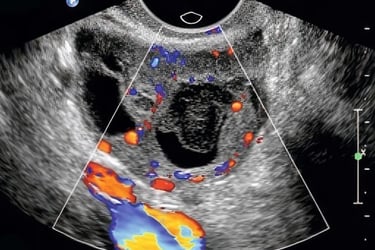

Hands-on practice emphasizes complete, systematic exams of the uterus, ovaries, adnexa, and Doppler assessment where indicated — each with faculty coaching on image optimization and interpretation. Brief reflective discussions bridge anatomy, physiology, and normal vs expected pathological findings.